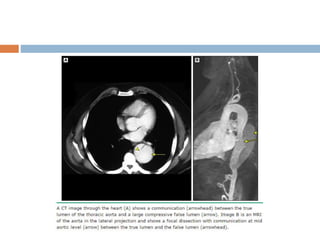

Aortic Disease

 Aortic root disease, leading to aneurysmal dilatation, aortic

regurgitation, and dissection - main cause of morbidity and

mortality

 Poor correlation between the severity of the cardiovascular

and the ocular or skeletal manifestations

 Although dilated, the aorta in MFS tends to be stiffer and less

distensible

 Dilatation of the aorta, often (about 25%) accompanied by

aortic regurgitation, progresses with time

50 percent of young children with MFS

60 to 80 percent of adult patients with MFS

 Dilatation may also involve other segments of the thoracic

aorta, the abdominal aorta, the root of the pulmonary artery

or even the carotid and intracranial arteries, although much

less frequent than in LDS.

 The normal range for aortic diameter varies with body size

and age - nomograms and Z-scores used to identify aortic

dilatation.

 Undiagnosed and untreated MFS - frequently associated with

aortic dissection. May have a family history of dissection.

 The frequency with which MFS is responsible for aortic

dissection varies with age.

50% of those under age 40

2 % of those with age 40 - 70

no patient over age 70